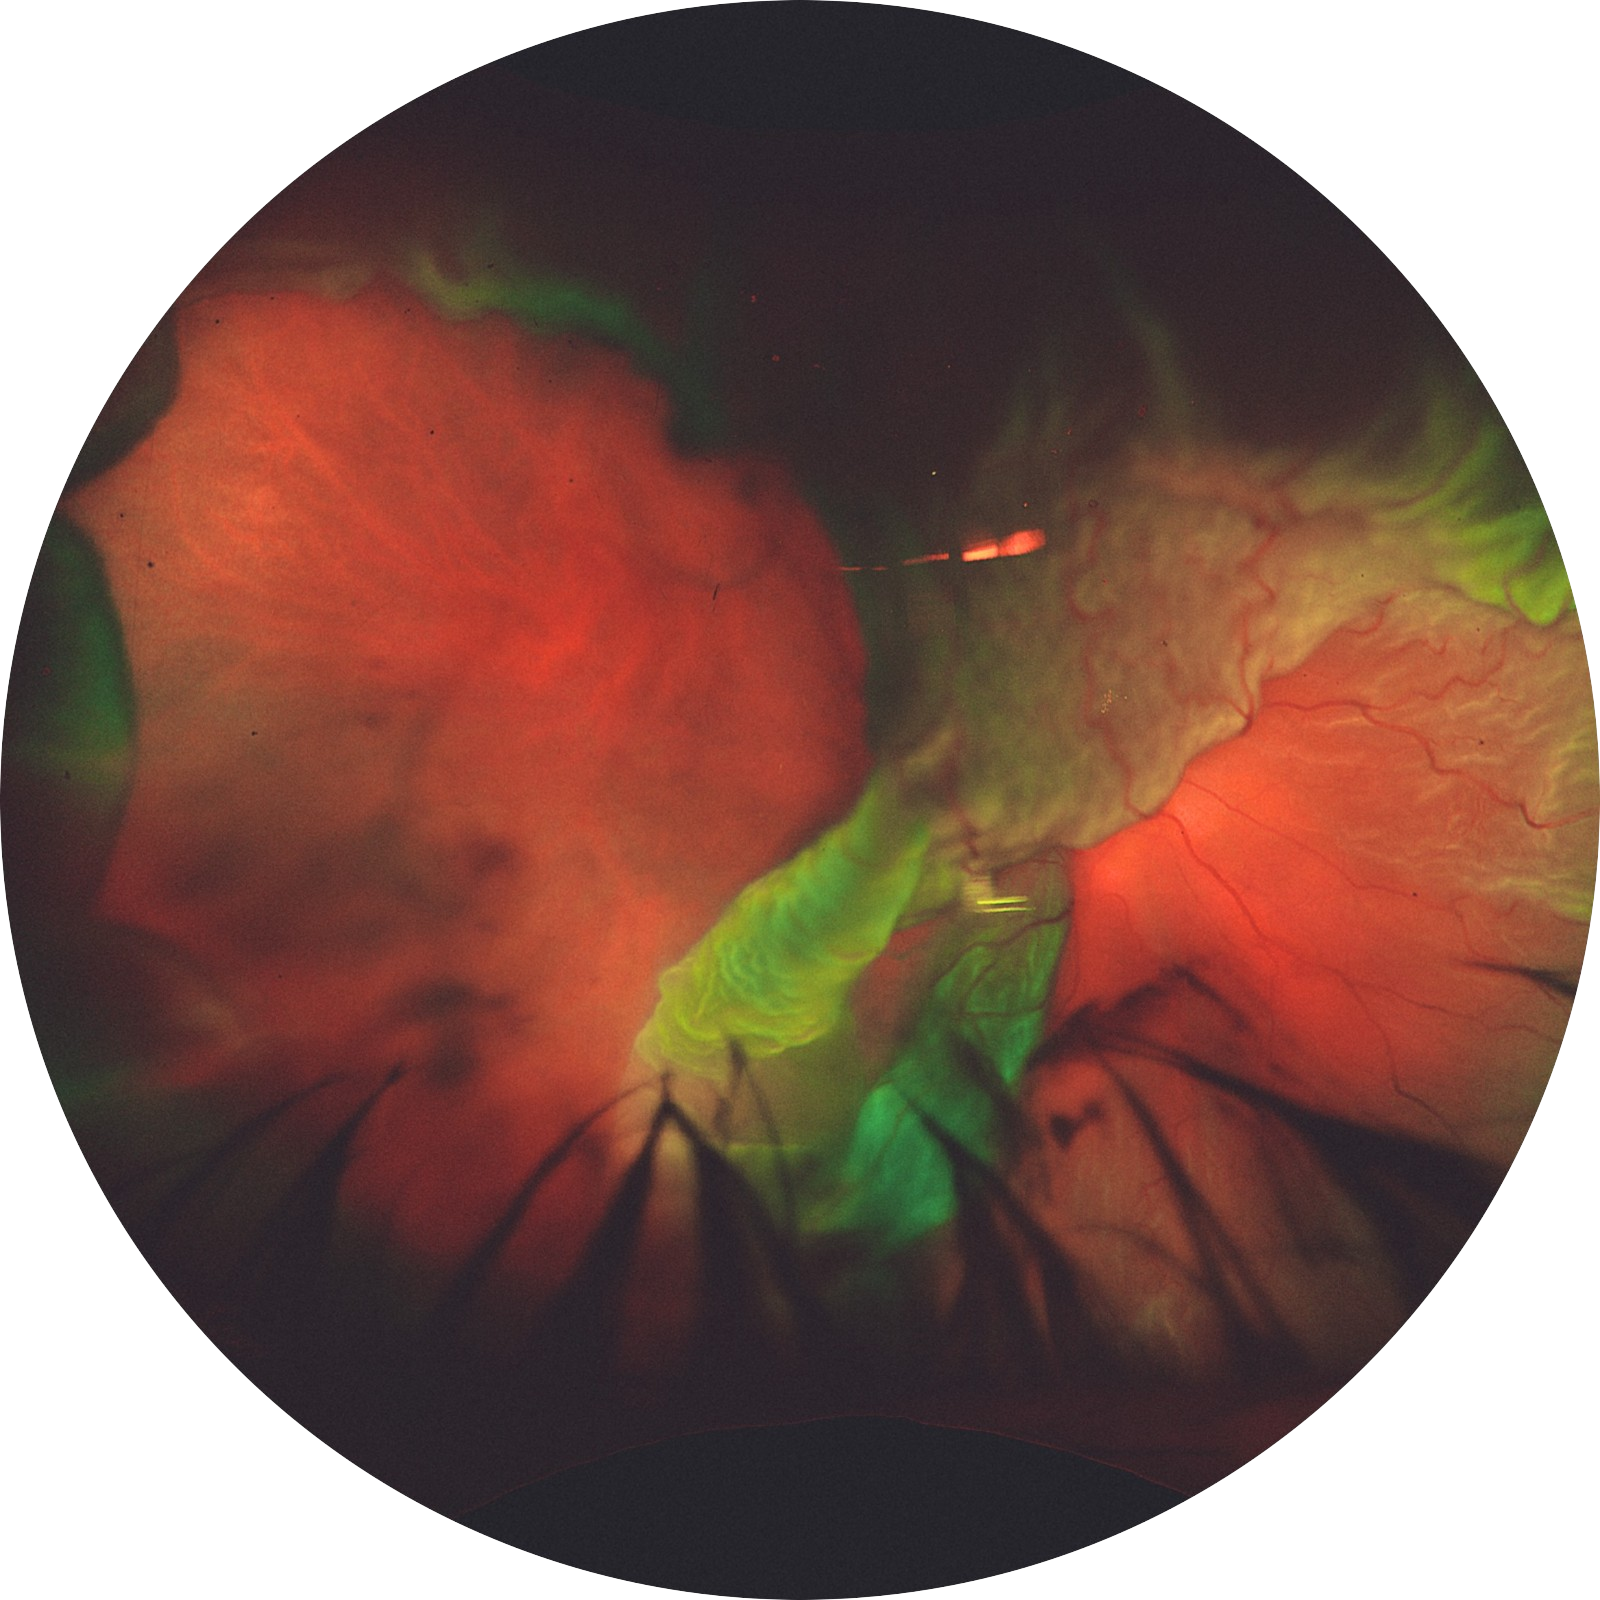

Title: Retinal Tornado: The Fury Of Giant Retinal Tear

Description:This is Optos ultrawide field retinal imaging camera image showing Giant retinal tear, the extent of tear starting from 7o clock to 11o clock (4 clock hours – 120 degrees). The whole temporal retina has detached and has inverted over like a flap. The rolled over retina resembles a tornado. It is as if tornado meets volcano depicting natures most explosive handshake